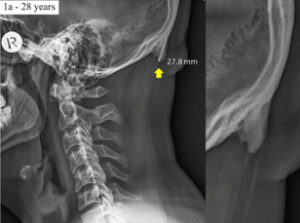

An interesting study done recently made headline around the world, “teenagers growing horns due to phone usage.” Whilst this did make me chuckle and was quickly dismissed by the main stream media, as a chiropractor with a keen interest in the mechanics of the neck, this makes sense, the body is responding to unnatural stresses placed on it, older generations are not developing the same changes and smartphone have only been available for ten years. Whereas I would’ve played Snake on my old Nokia 3210 and sent the odd SMS, now teens and even adults can easily spend hours on their various apps.